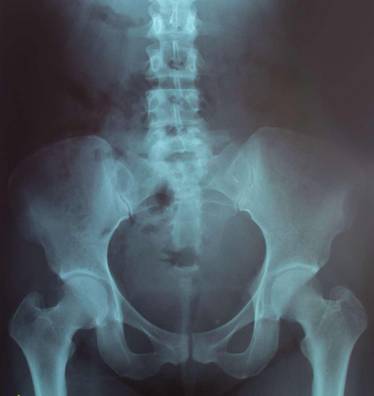

X光透视

提到X光透视,很多人的第一反应是想到它对人体的危害,但其实,在检查过程中的辐射量是微乎其微的,而且它也是现代医疗检查中必不可少的一种检查手段。

X光透视的优势也是别的检查无可取代的,其简便易行,能立即得到检查结果,可同时观察器官的形态和功能。常做的X光检查有:胸部X光和消化道造影。